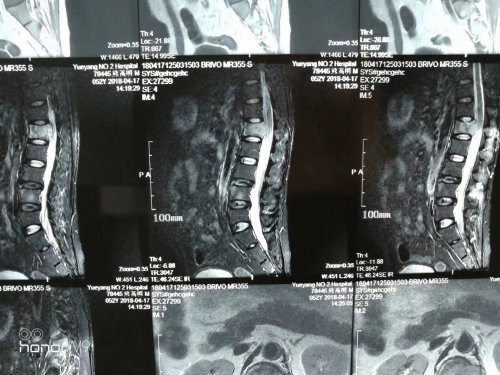

成x仙,女,31岁,因肝癌,肝硬化腹水晚期而入我院。诉:腹胀除夕前起,近月余,行背部推按锤击,前胸部不适即可缓。腰部锤击后,矢气做而腹胀暂消。面目萎黄,精神可,纳差,睡眠差。小便靠西药维持(不吃则少或无)。畏热无汗。余尚可。舌暗淡,苔白腻,脉(左)沉数细,(右)沉数涩。

此镜面人,临床罕见,发与此,供各位老师参考,同时也希望得到老师的指导。